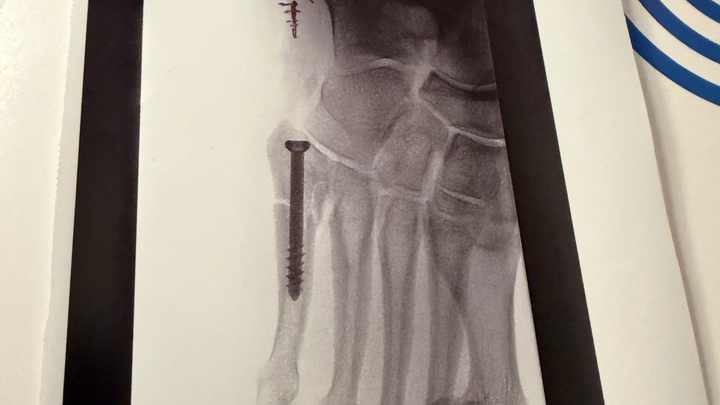

I recently took a trip down the stairs while trying to bring my sick roommate something. I missed the last step, twisted my ankle, and broke my foot. I have what’s known as a Jones Fracture and it needs surgery!